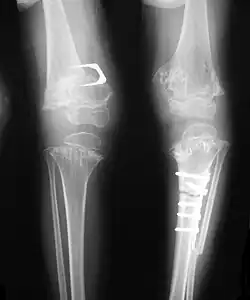

- Together with rhizomelic limb shortening, the presence of epiphyseal-metaphyseal changes of the long bones is a distinctive radiologic feature of pseudoachondroplasia.

- Dysplastic/hypoplastic epiphyses especially of shoulders and around the knees.

- Metaphyseal broadening, irregularity and metaphyseal line of ossification. These abnormalities that are typically encountered in proximal humerus and around the knees are collectively known as "rachitic-like changes".

- Radiographic lesions of the appendicular skeleton are typically bilateral and symmetric.